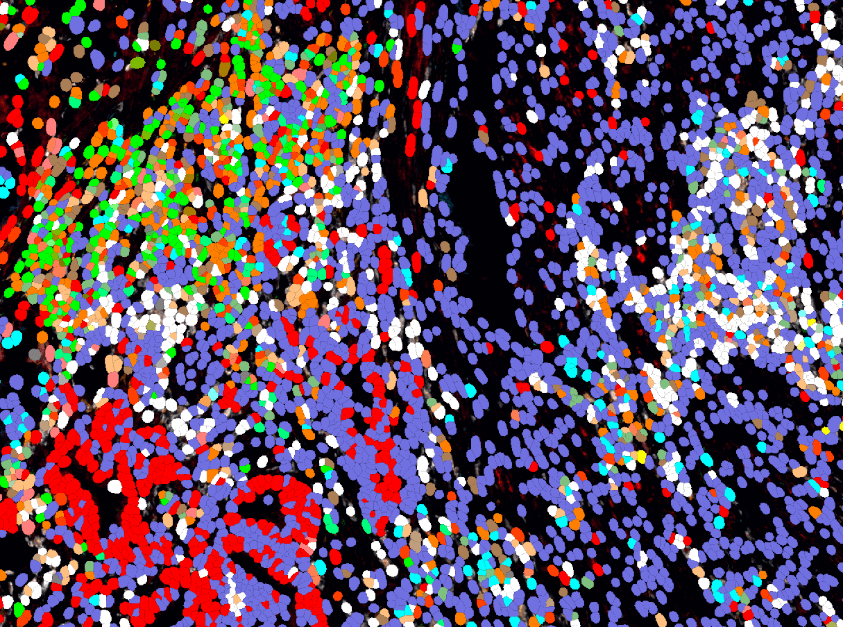

高精度强训练AI模型,精准划分区域并识别细胞,省去人工参数设置繁琐步骤

区域分类

空间关系分析